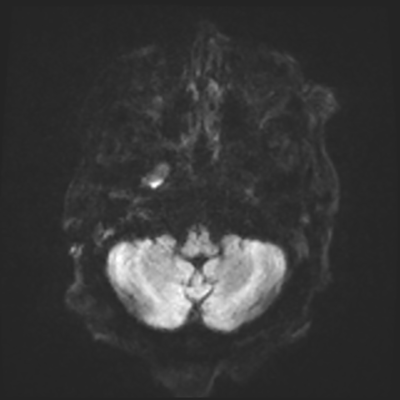

You come back the next day and see how things are going. The patient's electrographic record has shown a moderate encephalopathy (diffuse slowing, disorganization) with frequent right posterior quadrant delta slowing. Based on this result, and an adequately improved clinical examination, you give the okay to proceed with obtaining an MRI of his brain. This is shown below.

MRI brain (DWI)